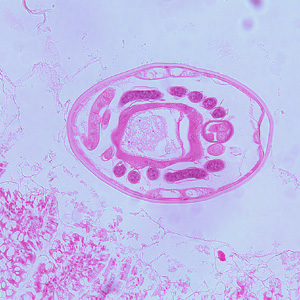

Hookworms in tissue, stained with hematoxylin and eosin (H&E).